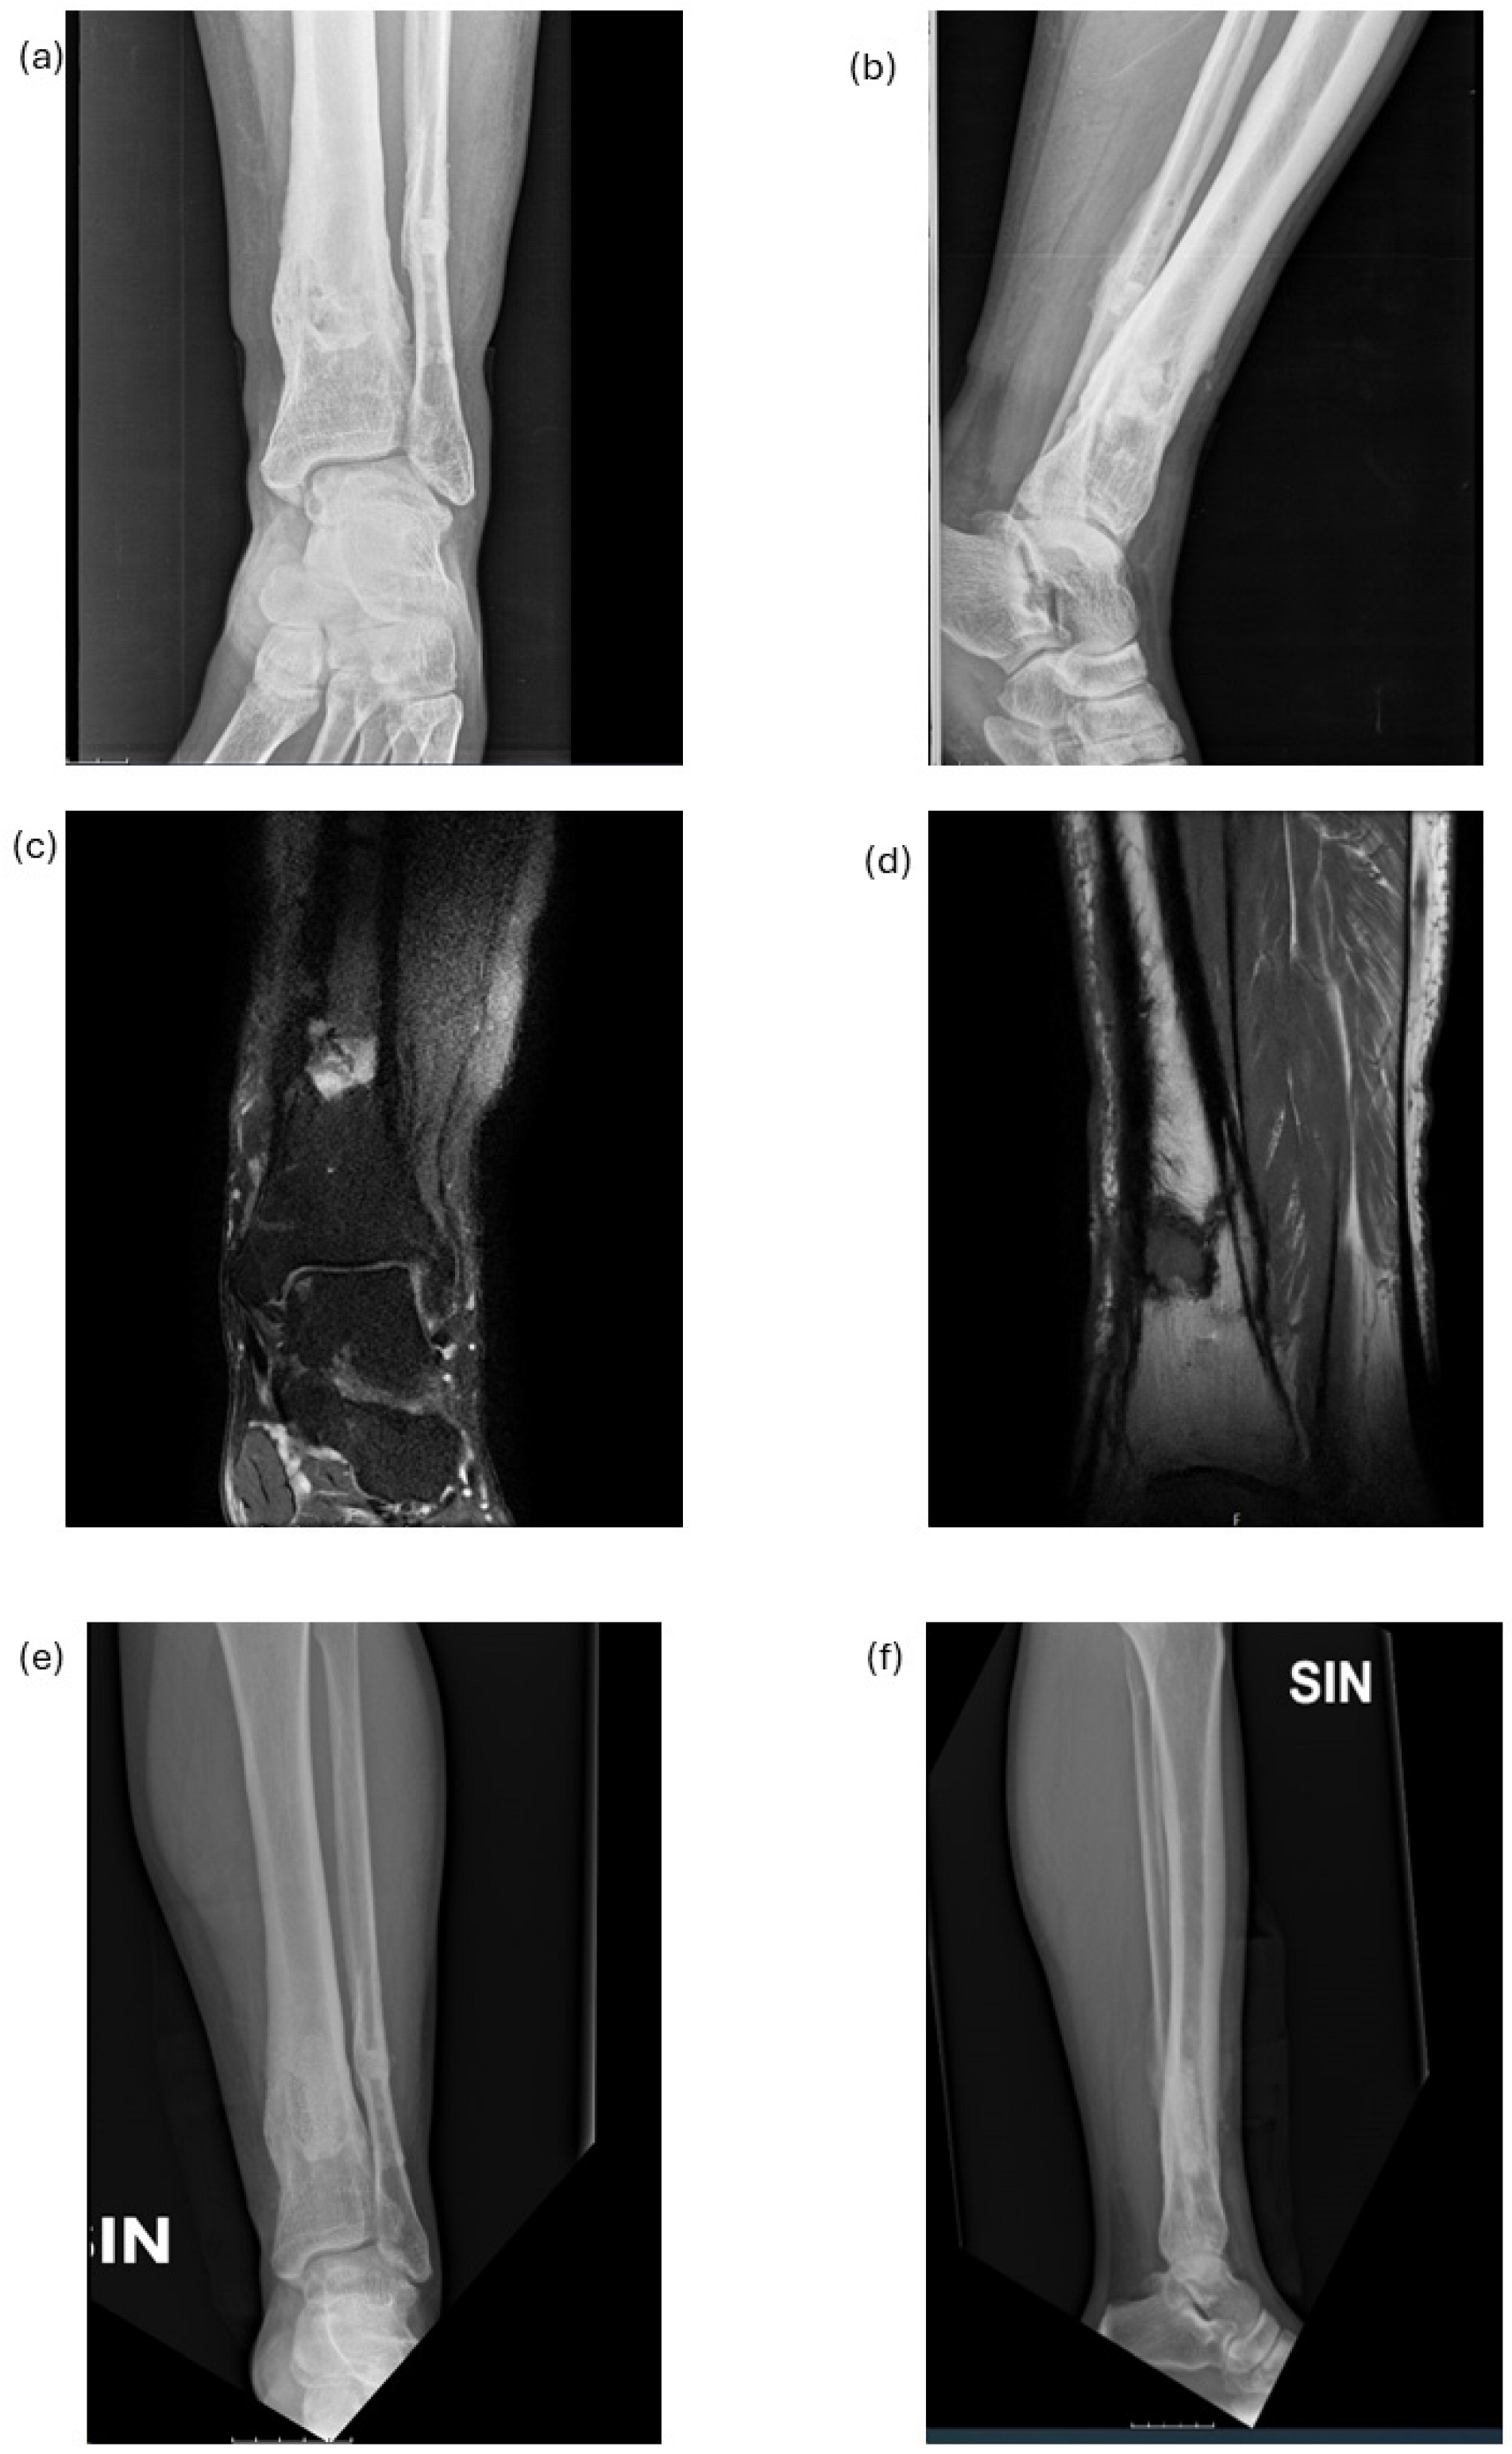

Once the diagnosis was made, the indication was given for elective surgical treatment of sequestrectomy and debridement of the osteomyelitis focus. The surgery performed can be summarized as follows: skin incision targeted to the pathologic portion of bone, skeletonization of the bone, the opening of a bone window with an appropriate saw to access the medullary canal, and subsequent thorough cleaning of the canal with the removal of any bone sequestration. Figure 5 reports examples of pre-operative and post-operative radiographic and MRI images of chronic osteomyelitis of the distal tibia: the post-operative images confirm the recovery of bone tissue compared to the pre-operative condition. Multiple tissue samples were collected in all patients for culture and histological examination.

Figure 5. Pre-operative and post-operative radiographic and MRI images of chronic osteomyelitis of distal tibia. Pre-operative radiographic AP (anteroposterior view, (a)) and LL (lateral view, (b)) images, and MRI AP (c) and MRI LL (d) images; post-operative radiographic AP (e) and LL (f) images.